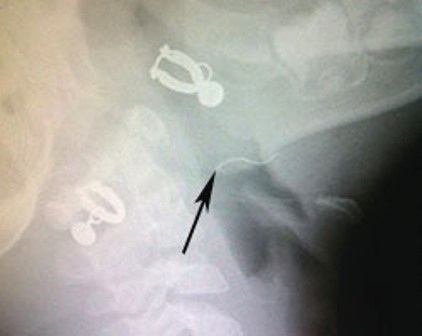

(Dân trí) - Ho sặc sụa, ói ra máu sau khi ăn cháo, bệnh nhi 4 tuổi được chuyển đến bệnh viện trong tình trạng uống khó, nuốt khó. Qua nội soi, bác sĩ phát hiện và gắp ra cọng kẽm đang găm vào amidan của bé.

Ngày 24/4 bệnh viện Nhi Đồng 1, TPHCM cho biết tại đây vừa can thiệp kịp thời cho một trường hợp bị hóc dị vật, ói ra máu, bệnh nhi là bé B.A. (4 tuổi, ngụ tại Tiền Giang). Theo khai thác bệnh sử gia đình cung cấp đến bác sĩ, trước đó cháu được mẹ cho ăn món cháo gà tại nhà. Sau khi ăn bé bị ho sặc sụa, khó thở nên được gia đình đưa đến bệnh viện địa phương kiểm tra.

Tuy nhiên, khi đến bệnh viện triệu chứng ho, khó thở của bé giảm hẳn. Bác sĩ kiểm tra không ghi nhận dấu hiệu bất thường nên cho bệnh nhi xuất viện. Một ngày sau, trong lúc đang học ở nhà trẻ, bé bất ngờ ho dữ dội và ói ra dịch có lẫn máu. Tá hỏa, giáo viên đã gọi điện báo cho gia đình, ngay sau đó bé được chuyển thẳng lên bệnh viện Nhi Đồng 1.